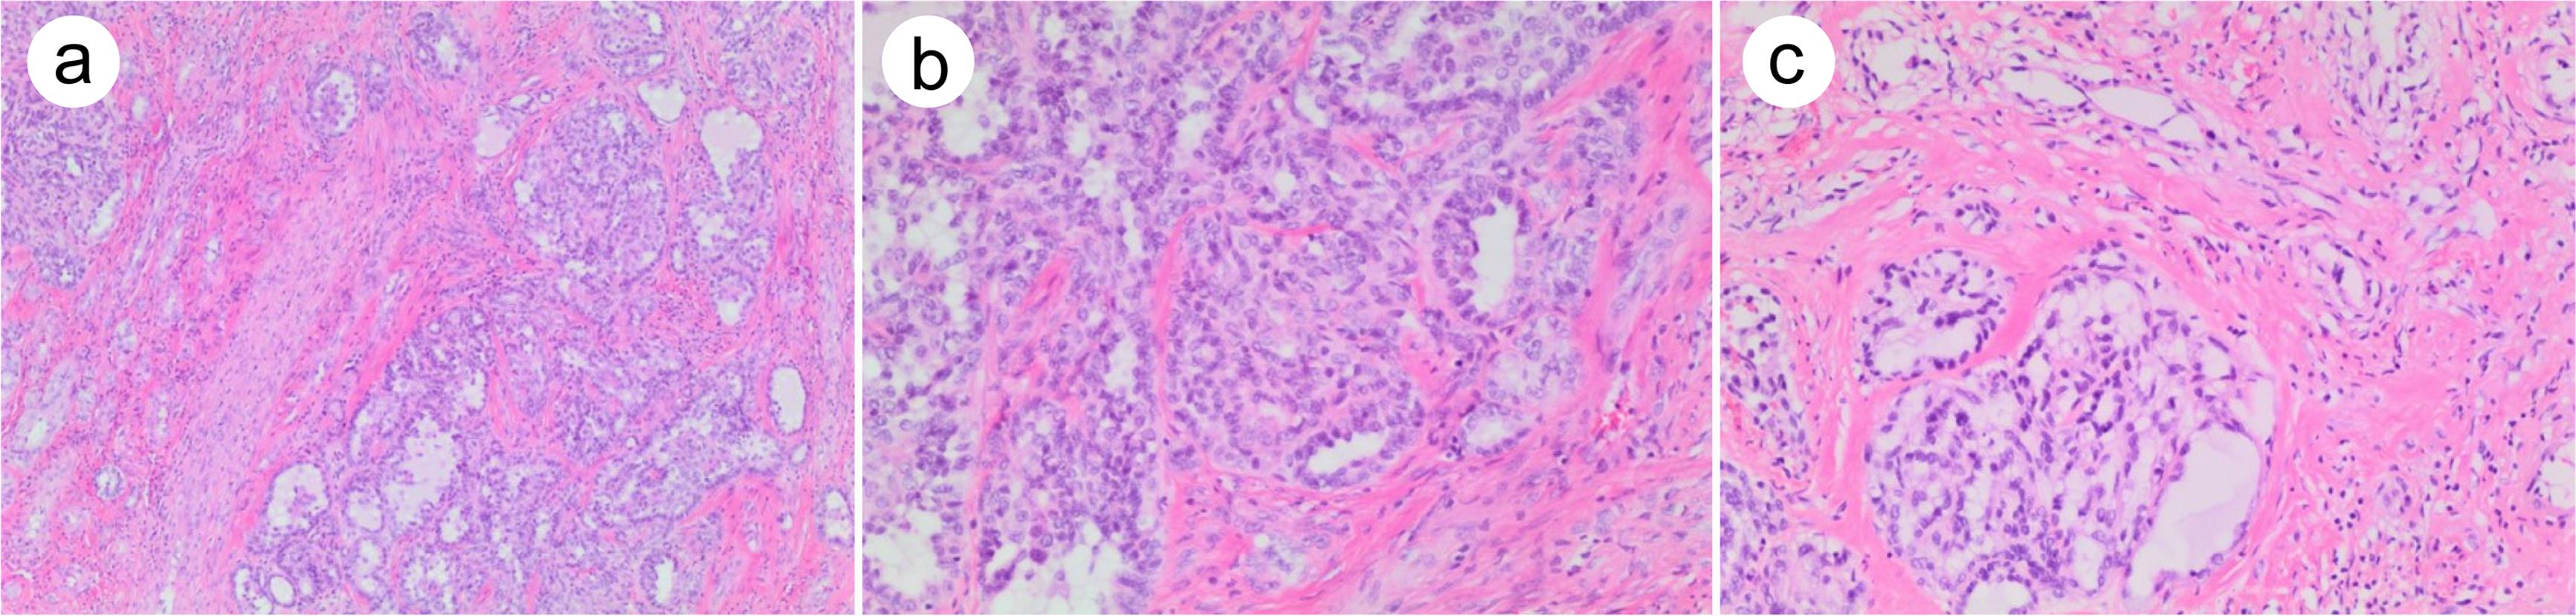

Although rhabdomyosarcoma accounts for the majority of sarcomatous SMs, other sarcomas may also arise from GCTs.12,15 SM with leiomyosarcoma is characterized by a fascicular growth pattern (bundles intersect at right angles) of high-grade atypical palisading spindle cells (Fig. 2a), eosinophilic fibrillary cytoplasm, and elongated or fusiform blunt-ended nuclei (Fig. 2b). SM with leiomyosarcoma can also show primitive apparency with no appreciable smooth muscle differentiation, in which tumor necrosis is commonly seen (Fig. 2c). SM with angiosarcoma shows infiltrative proliferation of pleomorphic atypical cells with anastomosing irregular vascular spaces. In addition, low-grade myoxid sarcoma, myxofibrosarcoma, and osteosarcoma also have been reported in SMs derived from GCTs.12,15,16

Fig. 2  Leiomyosarcoma arising from teratoma.

(a) Malignant spindle cell proliferation with a fascicular growth pattern. Note the residual teratomatous (cartilage) component in the right lower corner. (b) Relatively well-differentiated area with atypical palisading spindle cells, eosinophilic fibrillary cytoplasm, and elongated or fusiform blunt-ended nuclei. (c) More primitive area with highly atypical cells and no appreciable smooth muscle differentiation. Note the tumor necrosis in the right upper corner.